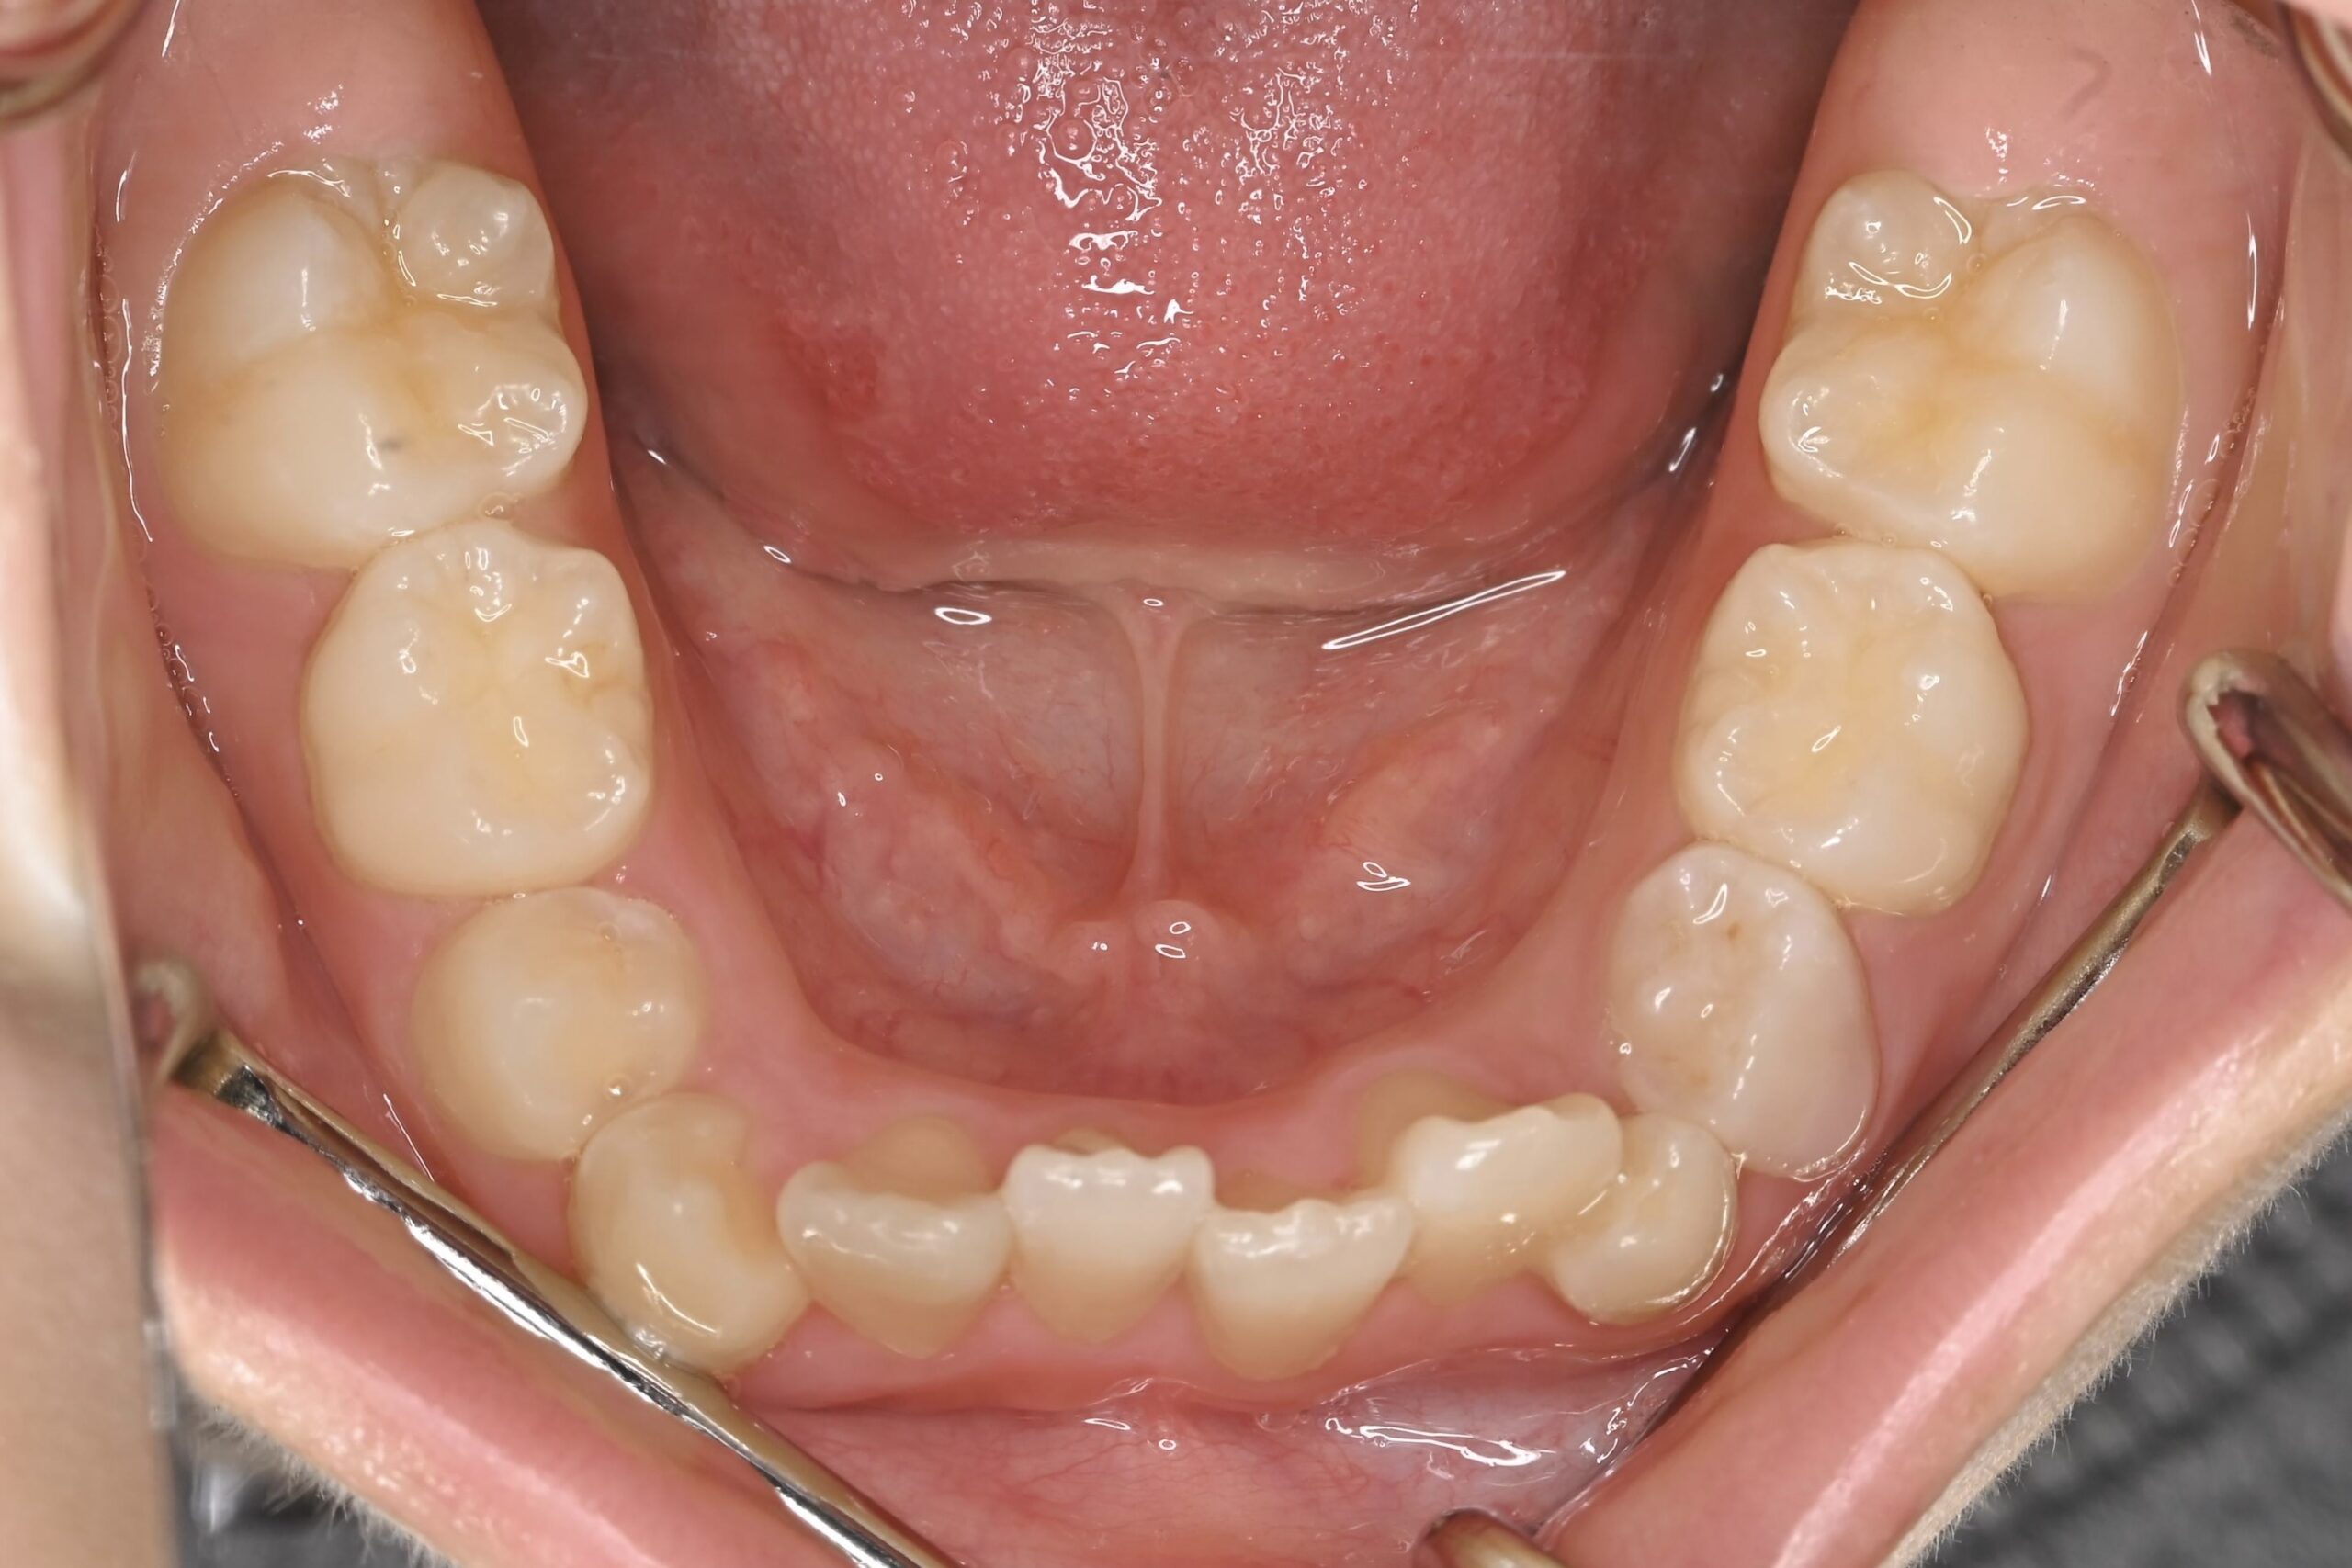

7歳 男児 小児矯正

BEFORE

AFTER

主訴 通っている歯医者で矯正した方がいいと言われて気になっている。下の前歯がでこぼこしている。

診断名・主な症状 下顎前歯の叢生を伴う過蓋咬合

治療内容 上下の歯並びの幅を拡げつつ、前歯の関係を改善しました。

使用装置 急速拡大装置

リンガルアーチ

機能的矯正装置(マイオブレース)

抜歯部位 抜歯なし

治療期間 2年 + 後戻り止め期間(3年 )

通院回数 20回

費用 50万円程度(税別)  29331

リスク・副作用 痛み、歯肉退縮、歯根吸収、抜歯に伴う出血や腫れが生じることがあります。